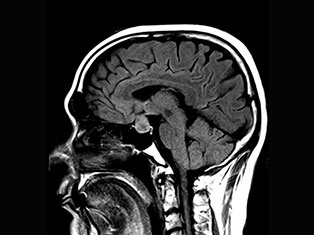

Brain Tumors

A brain tumor is a mass or growth of abnormal cells in your brain. Many different types of brain tumors exist. Some brain tumors are noncancerous (benign), and some brain tumors are cancerous (malignant).